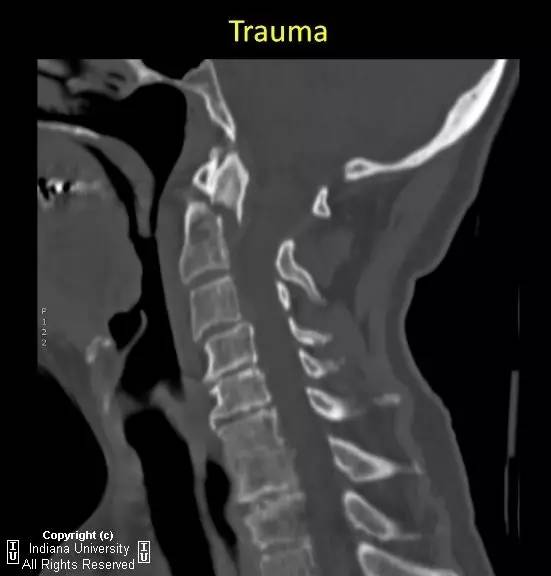

【病例】II型齿状突骨折1例

【影像学表现】

急性横行齿突骨折,C2椎体与齿突尖分离约7mm。齿突尖仍与C1前弓正常排列。

【诊断】II型齿突骨折

Type 2 odontoidprocess fracture